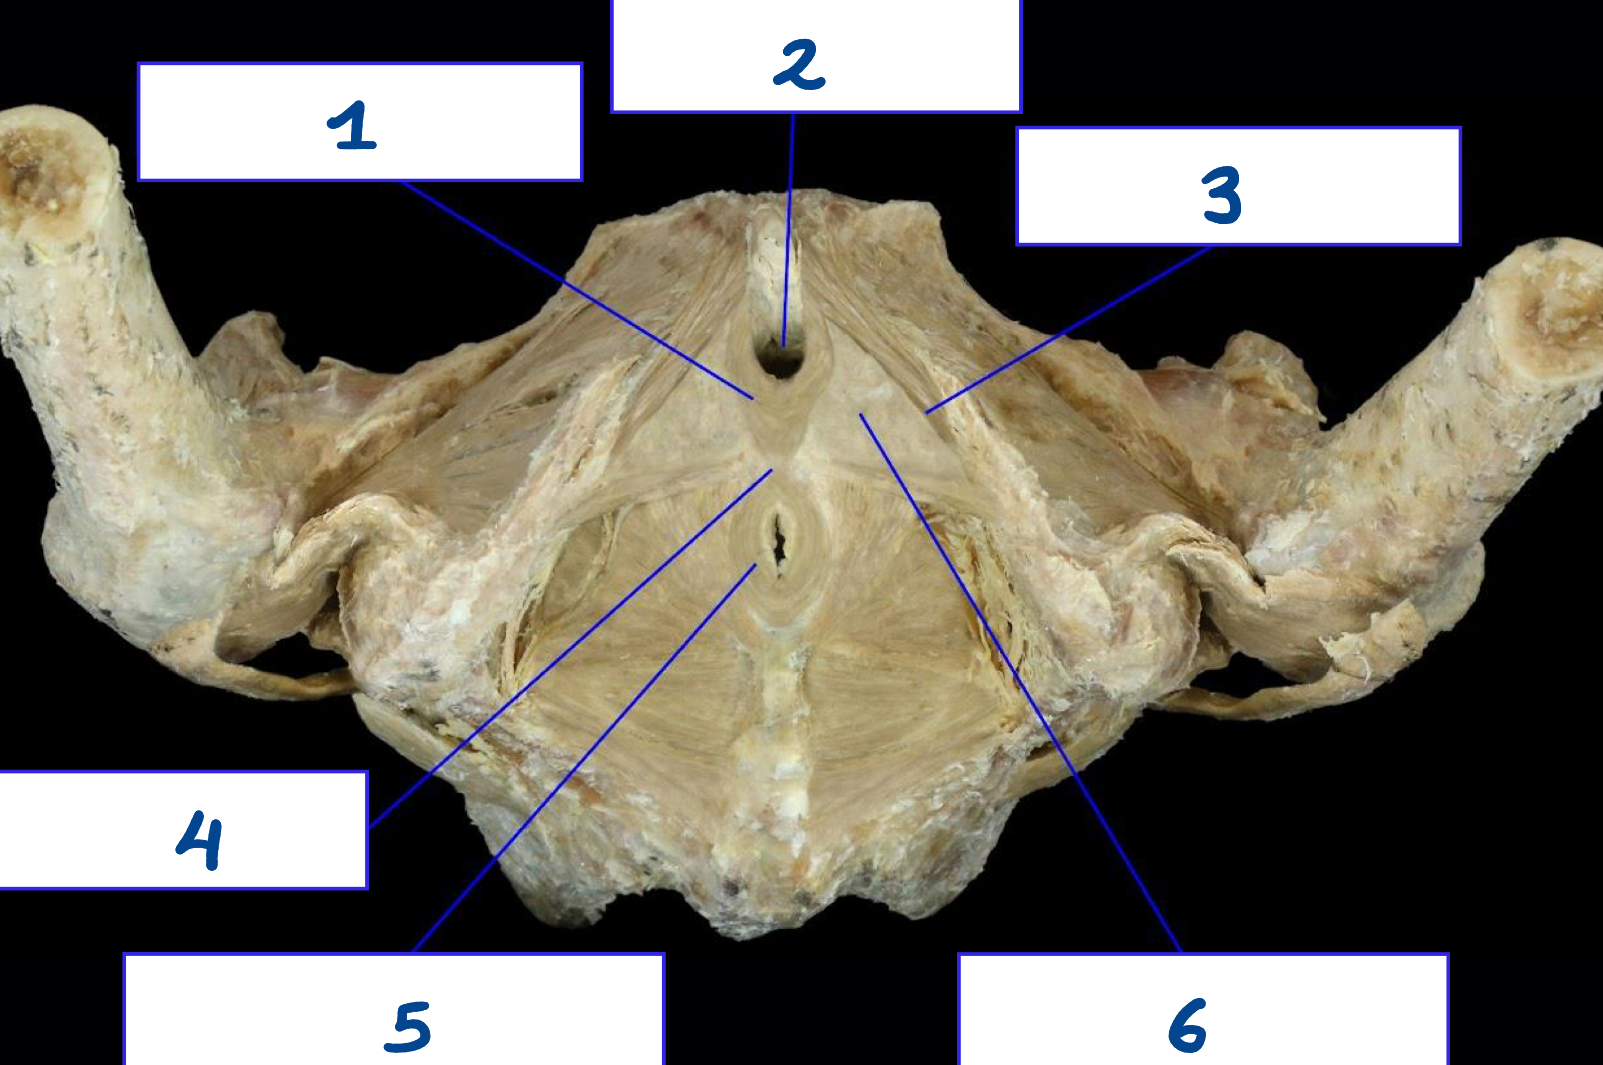

<p>What is structure 1?</p>

What is structure 1?

Sacrospinous ligament

<p>What is structure 2?</p>

What is structure 2?

Sacrotuberous ligament

<p>What is structure 3?</p>

What is structure 3?

Greater sciatic foramen

<p>What is structure 4?</p>

What is structure 4?

Lesser sciatic foramen

Urogenital triangle

Pubic symphysis

Ischiopubic ramus

Anal triangle

<p>What is structure 5?</p>

What is structure 5?

Coccyx

<p>What is structure 6?</p>

What is structure 6?

Ischial tuberosity